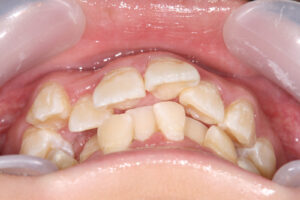

よく観察してみるとリラックスした状態では口唇が完全に閉鎖しきれず、上前歯が口元から少し見えています。

動物のビーバーをイメージすることから、『ビーバーちゃん』という昔は可愛くて少しは好きだったあだ名も、

最近ほそう呼ばれるのがなんとなく憂鬱だと言っていました。そのため、いつもは意識して口唇を閉鎖しているそうです。

口元が閉じた状態では明らかに口輪筋とオトガイ筋が緊張しており、側方からみると口元が少し出っ張っている感じです。

この患者さんは、主に上顎が優勢であり、上下歯列は理想的な位置より前に出てきてしまっています。

前方に出過ぎてしまった前歯を舌側へもって行くということは、同時に歯槽骨を改善されるわけですから、

ベースとなっている上顎骨がやや大きくても、歯を移動させることによって、カムフラージュすることになります。